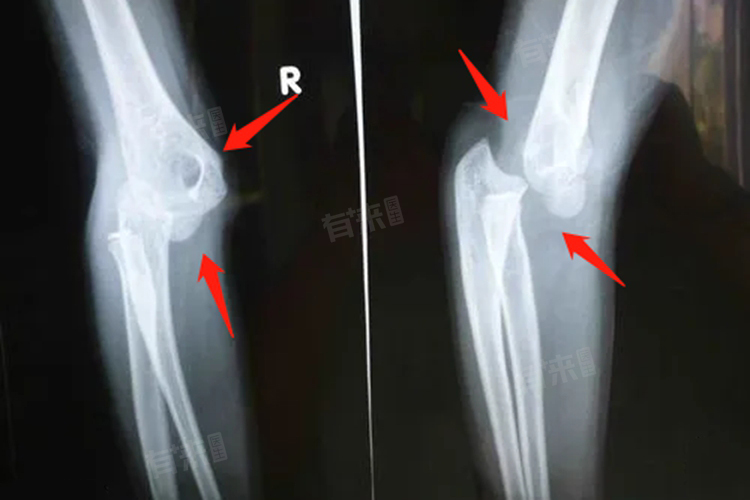

2、查看肢体外观:仔细查看孩子疑似脱臼部位的肢体外观,脱臼时,关节可能出现畸形,比如肘关节脱臼后,肘部会呈现不自然的弯曲或扭曲;肩关节脱臼时,肩部可能变得平坦,与正常形态有明显差异。同时,受伤部位还可能出现肿胀,皮肤颜色也可能变红。